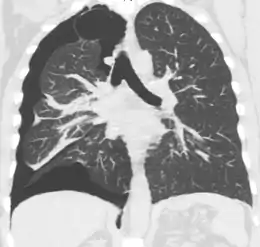

Computed tomography

CT with the identification of underlying lung lesion: an apical bulla on the right side

A CT scan is not necessary for the diagnosis of pneumothorax, but it can be useful in particular situations. In some lung diseases, especially emphysema, it is possible for abnormal lung areas such as bullae (large air-filled sacs) to have the same appearance as a pneumothorax on chest X-ray, and it may not be safe to apply any treatment before the distinction is made and before the exact location and size of the pneumothorax is determined.[15] In trauma, where it may not be possible to perform an upright film, chest radiography may miss up to a third of pneumothoraces, while CT remains very sensitive.[18]

A further use of CT is in the identification of underlying lung lesions. In presumed primary pneumothorax, it may help to identify blebs or cystic lesions (in anticipation of treatment, see below), and in secondary pneumothorax, it can help to identify most of the causes listed above.[15][19]